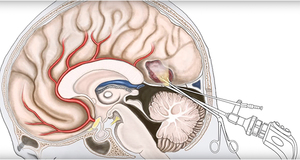

Большие опухоли в головном мозге удаляются хирургическим способом. Это наиболее радикальный метод лечения. Операции выполняются различными техниками:

- Трепанация черепа. В ходе этой процедуры вскрывается череп пациента, и кистозное образование удаляется полностью. Рецидивы кисты, как правило, не возникают. Этот метод считается очень эффективным, однако он также является наиболее травматичным.

- Шунтирование. В черепе делается небольшой прокол, через который устанавливается дренажная трубка в полость кисты. С помощью дренажа осуществляется отток жидкости из кистозного образования. Киста уменьшается в размерах, и со временем её стенки рассасываются. Этот метод менее травматичен по сравнению с трепанацией, но существует риск инфицирования.

- Эндоскопический метод. В черепе создается прокол, через который вводится эндоскоп — небольшой прибор с видеокамерой. Удаляется содержимое кистозной полости, а её стенки со временем рассасываются самостоятельно. Это самый безопасный способ удаления, однако не все виды кистозных образований можно удалить таким образом.